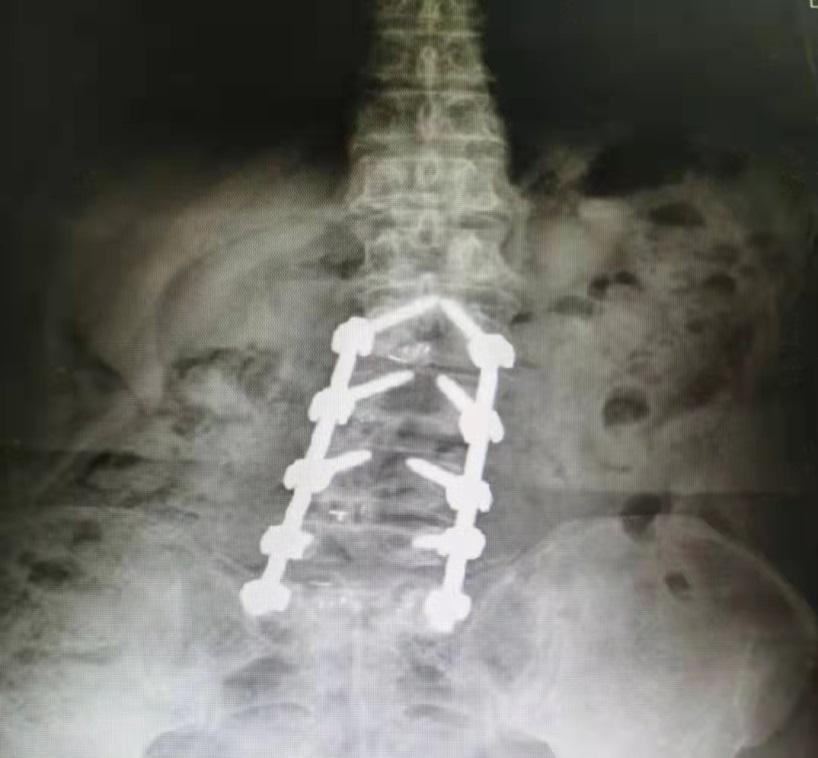

那么李阿姨的腰椎到底弯到了什么程度呢?大家可以看一下:

第二,光是脊柱侧弯导致走路不好看也就算了,最关键是脊柱侧弯导致严重的椎间盘突出、骨质增生,身体形态改变导致髋关节、膝关节受力改变,慢慢的都出现关节变形,腰疼、髋关节疼痛、膝盖痛的毛病一个跟着一个都来了。

其中最难熬的就是腰疼,腰椎是人体负责承上启下的主要结构,其中相关的血管、神经、肌肉不计其数,李阿姨的腰椎侧弯非常严重,还是扭转弯的那种,就跟拧了个麻花似的,可以想象里面的神经都被压成什么样子了。